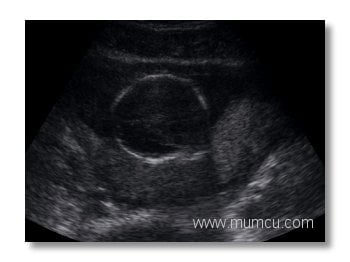

5 haftalık gebelikte gestasyonel kese

Vajinal ultrasonografi